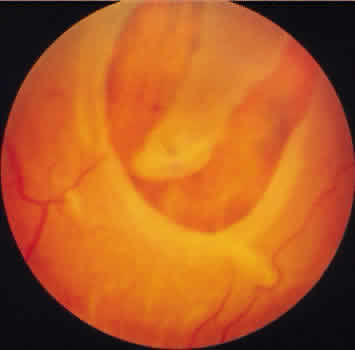

Retinoschisis associated with a bullous architecture and prominent reticular cystoid degeneration has been termed reticular degenerative retinoschisis. Reticular degenerative retinoschisis can be distinguished from typical degenerative retinoschisis by the large extent of retinal involvement, a round or ovoid configuration with bullous elevation of the extremely thin inner layer, and an irregular, pitted outer layer (Figs. 20 and 21). Typical cystoid degeneration is always present anterior to the schisis; reticular cystoid degeneration is usually prominent at some site in the involved eye. Blood vessels coursing through the inner layer give it an arborizing reticular pattern on contact lens biomicroscopy. The intraretinal cavity is optically empty; the outer wall is irregularly excavated to produce a pocked or honeycomb appearance. Round or ovoid holes are often present in the outer retinal layer; they are single or multiple, frequently large, and usually associated with a rolled posterior edge.13

Fig. 20. Reticular degenerative retinoschisis. Note reticulated, highly elevated, inner wall with a conspicuous delicate vascular pattern. Radial columns of the retina are completely disrupted within the region of bullous elevation, and the retinoschisis extends posterior to the equator. (× 18.)

Fig. 21. Clinical appearance of reticulardegenerative retinoschisis: diagram of involved area and photographs of ocular fundus showing optic disc, macula, and posterior portion of the schisis. These illustrate outer layer retinal breaks, adjacent retinal pigment epithelium abnormality, and a lo-calized nonrhegmatogenous retinal detach-ment.

Microscopic sections demonstrate the extremely attenuated, blood vessel-containing inner layer composed of the internal limiting membrane and remnants of the nerve fiber layer (Fig. 22). The honeycomb appearance of the outer layer corresponds to irregular excavations. In some areas, the outer layer is made up of outer plexiform, outer nuclear, external limiting, and rod and cone layers; in other areas it is reduced to only the external limiting and the rod and cone layers; round or ovoid holes may be present (Fig. 23).

Reticular degenerative retinoschisis is evident in 1.6% of adult patients, is bilateral in only 16% of these, and thus is noted in 0.95% of adult eyes (see Table 3). The lesion is found most commonly in the inferior temporal quadrant. A band of typical cystoid degeneration always separates the schisis from the ora serrata; the schists usually reaches the equator and often extends appreciably into the posterior retina.

On contact lens biomicroscopy, many retinal blood vessels present irregular contours, telangiectases, occluded segments, and microaneurysms. Between these vessels, the inner wall has a finely textured appearance and variable white, glistening particles on the vitreous side. The outer retinal wall is best seen when scleral depression produces a “white with pressure” phenomenon and reveals the honeycomb appearance. The retinal pigment epithelium often has a granular, salt-and-pepper appearance, and outer-layer retinal breaks are common. These breaks are particularly likely near the anterior and posterior margins of the schisis.

Treatment for reticular degenerative retinoschisis is rarely necessary.15 Treatment is indicated when the schisis cavity is symptomatic or progressive and associated with a rhegmatogenous component from both inner and outer wall retinal holes.15 Surgical management has included: external drainage ofsubretinal fluid with simultaneous intraocular gas injection,16 pars plana vitrectomy with either limited inner wall retinectomy and internal drainage through preexistent outer wall holes17 or with perfluorocarbon liquid assisted anterior displacement of subretinal fluid.18 No treatment is indicated for nonprogressive reticular degenerative retinoschisis that does not extend toward the macula. Photographic documentation of the posterior borders of the retinoschisis cavity may be useful in clinical monitoring for progression.